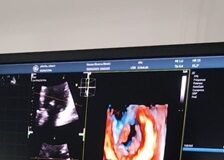

Arriva a Rimini un ecocardiografo di ultima generazione

RIMINI - Arriva sul territorio riminese un ecocardiografo di ultima generazione che grazie a nuovi software permette esami tridimensionali, la misura precisa del grado...